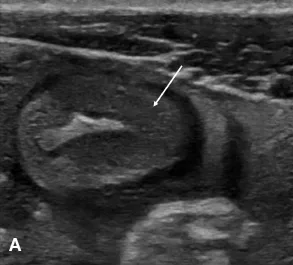

Figure 1. Patient de 19 ans présentant une poussée aiguë de maladie de Crohn.

A. Échographie en coupe axiale de l’anse montrant un épaississement pariétal de la dernière anse iléale avec perte des couches et aspect globalement hypoéchogène.